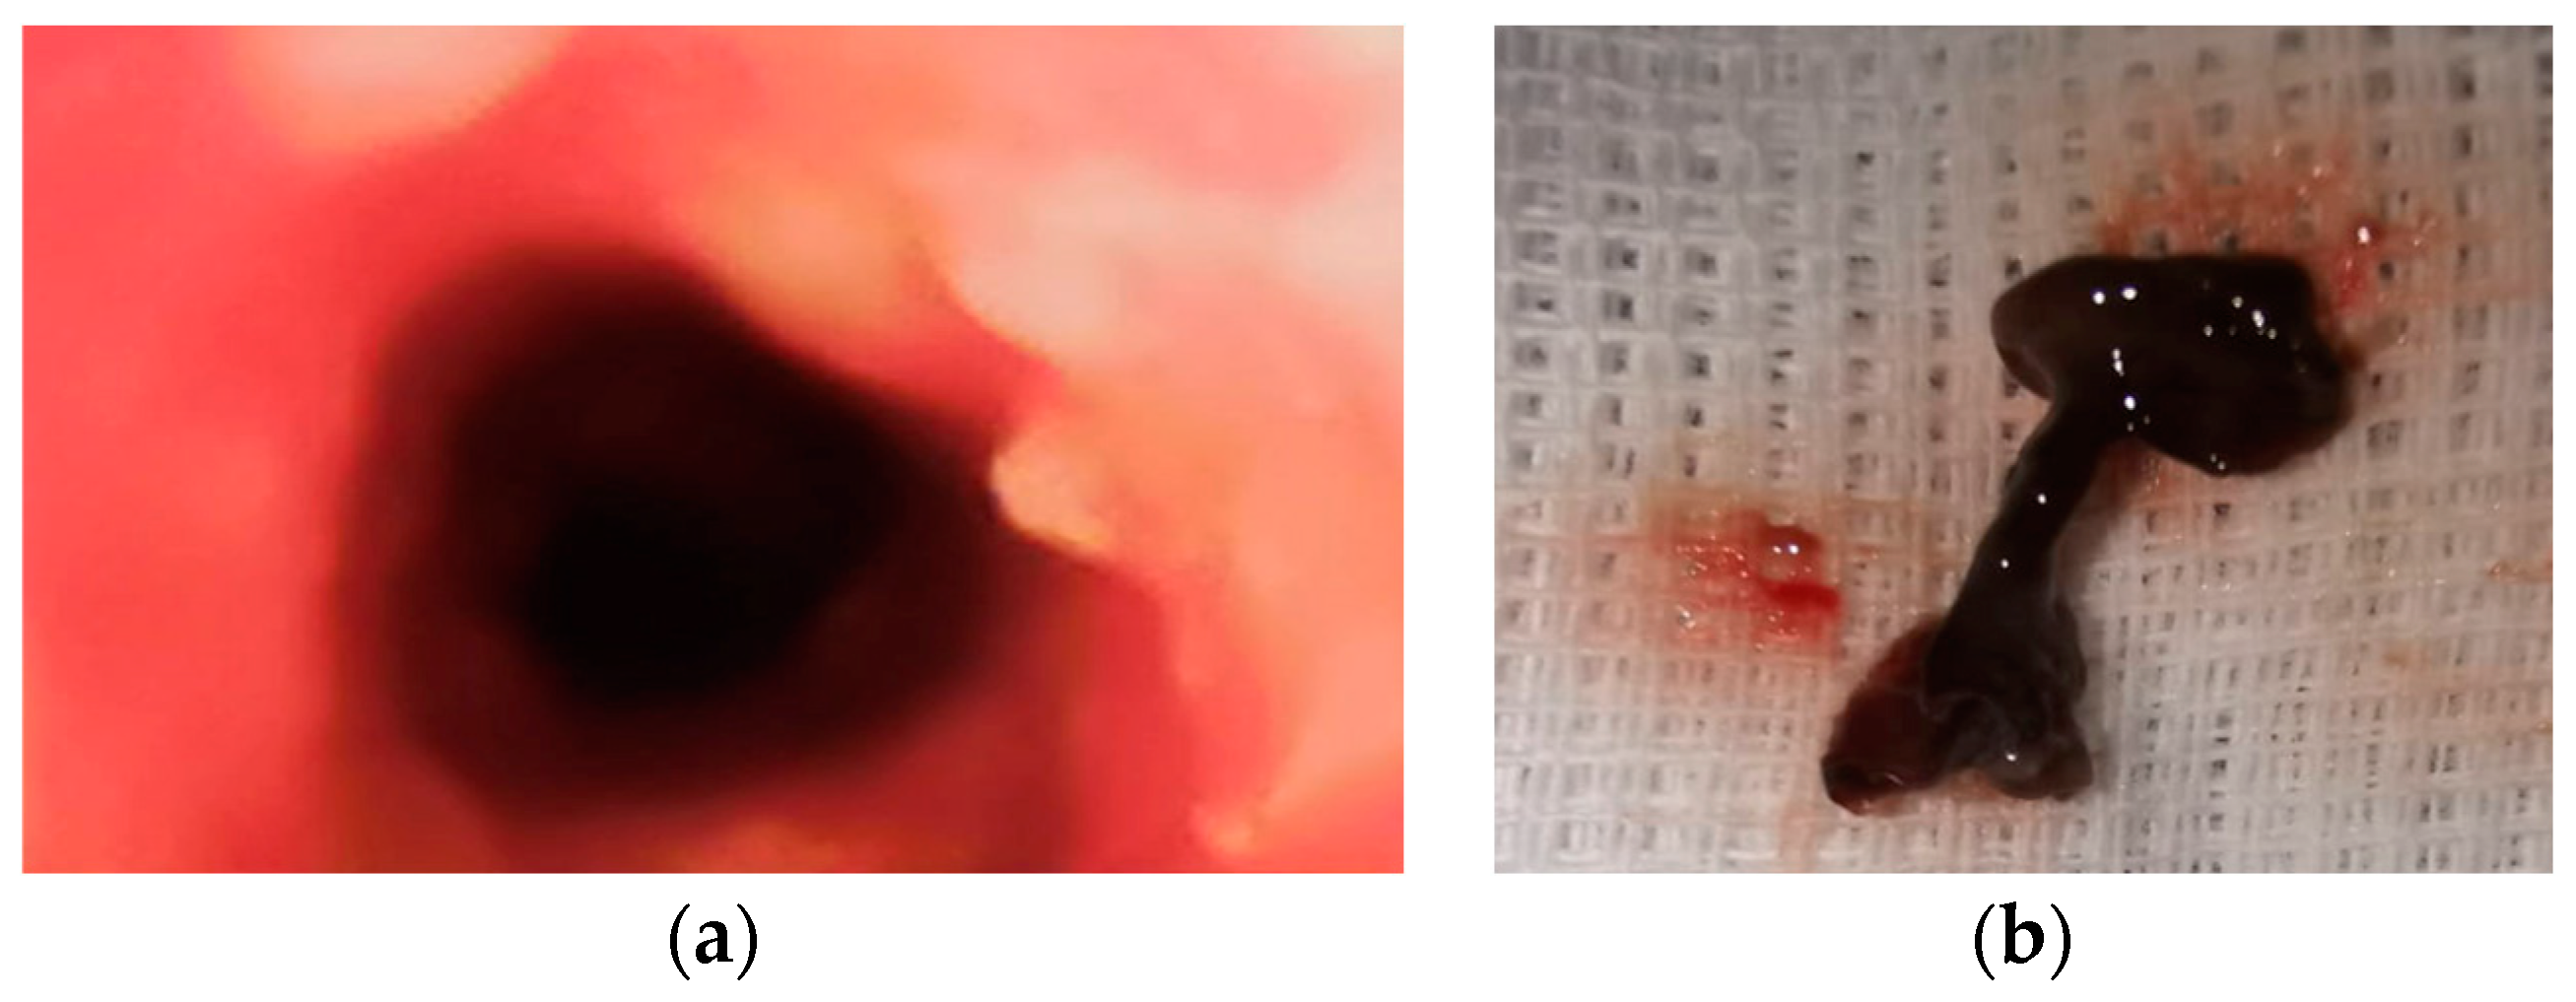

During the 7th day in ICU, the postoperative wounds were reviewed. Local evolution was favorable, and fascial necrosis and pathological secretions were absent. Granulation tissue is present in the wound. These aspects led us to the decision of finally closing the wound (wound secondary sutures) and of suppressing the remaining drain tube located in the anterior mediastinum (Figure 3).

Figure 3. (a) Absence of the local fascial necrosis and pathological secretions and (b) wound secondary sutures and the last drain tube located in the anterior mediastinum that was removed.